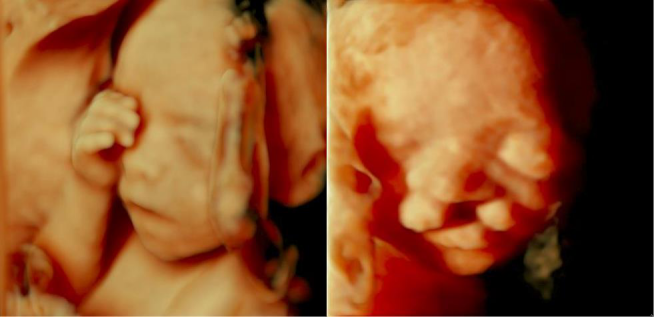

中孕期彩超胎儿颜面部及脊柱成像,把胎儿看的真真切切,明明白白,让您提前观察到宝宝的一举一动,一颦一笑,准妈妈们可以亲眼目睹胎儿在子宫内的相貌和动作,在感叹生命发生的同时,留下一段珍贵的影像,一段属于您和宝宝最早最珍贵的回忆。

生气了 哈哈-- 睁眼睛了

思考一下 光太亮了 好好睡一觉吧

做了个好梦 别惹我

胎儿脊柱成像 看我的脚丫子胖不胖····

挠一挠 唇裂

故三维、四维容积超声对诊断胎儿神经系统学,表面成像的胎儿畸形的筛查有更直观的感受,更明确的帮助诊断。